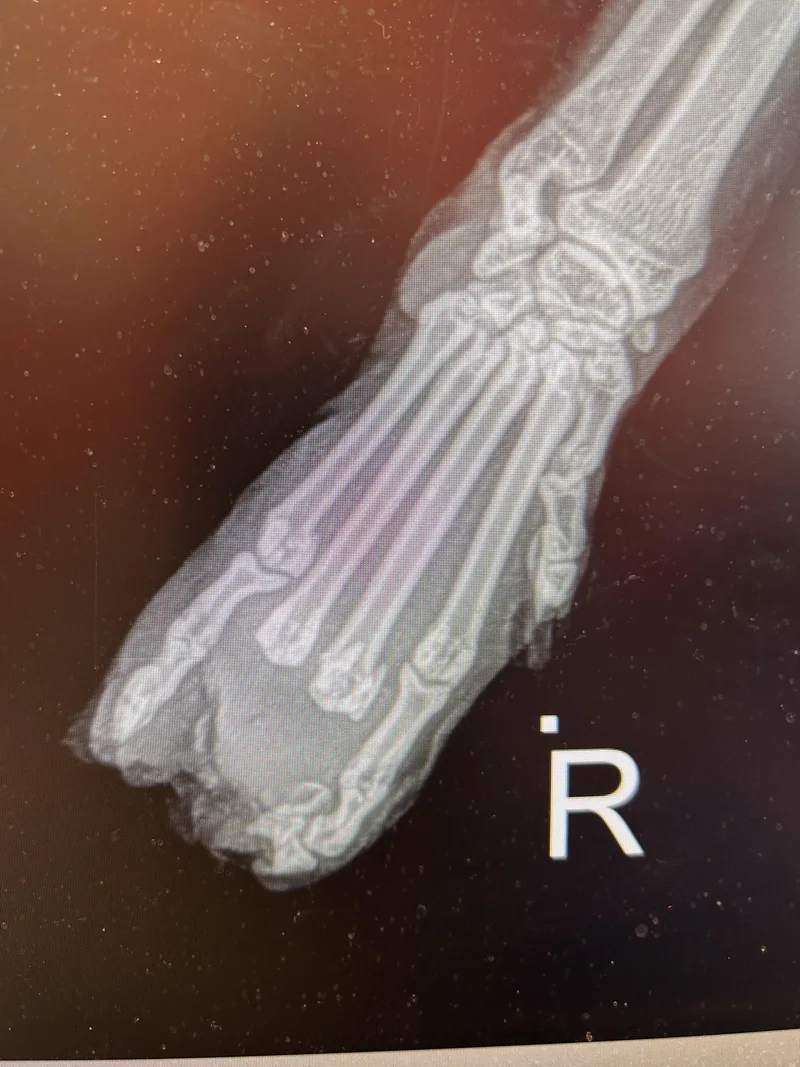

Kenzo, the Little Dude with the Crab Claw I could have named him “Mork from Ork” or gone all-in with “Nanu-Nanu,” but this time I chose a more dignified path. Kenzo is a Japanese name meaning healthy and wise, often formed from elements like ken (strong, healthy, wise) and zo (creation, thrive, three). It symbolizes vitality, growth, and good fortune—and from the moment he arrived, I knew he needed a name that would usher him into a new year filled with strength and healing. Kenzo came to me on December 15th, after being found the night before at the end of an ice-cold boat dock in Ada. He was malnourished, frightened, and suffering from a debilitating injury that resulted in lack of blood flow and severe frostbite to his right forepaw. It didn’t take long to realize that this little guy had endured far more than his fair share—and that he was determined to survive it. As it turned out, two of his five digits could not be saved and ultimately required amputation, leaving him with three toes to carry him forward. That alone sealed it: Kenzo was the only name that fit. Despite weighing just 7 pounds—far too small for a two-year-old male—Kenzo proved himself to be a sturdy little fighter. Unfortunately, he was also hosting far too many unwanted guests. Ear swabs revealed an active infestation of ear mites deep within his canals (the microscopic videos were truly disgusting), and his gastrointestinal tract was burdened with both roundworms (common) and lungworm (uncommon). Thankfully, treatment is highly effective, and within days his severe diarrhea resolved, and his weight began to climb. Before surgery could even be considered, Kenzo required strong systemic antibiotics and pain control. Initially, I removed necrotic skin from his damaged foot, along with the most distal bones—the third phalanges—which detached along with the dead tissue. The exposed bones were carefully bandaged and protected while the antibiotics had time to work. A bacterial culture later revealed a deep, aggressive infection that had spread into the bone itself, making surgery unavoidable. A few days later, I removed the remaining four phalanges of the two affected digits. I’m happy to report that Kenzo sailed through surgery with flying colors and soon returned to Crash’s to begin the cushy, comfortable life he was long overdue for. Kenzo is still a bit skittish when he is first approached, but he improves every day. He loves chasing toys, zooming through tunnels, and has been spotted playing with Cannon and several of the other more active cats—it’s adorable how naturally he fits right in. Because he may be a quick door-darer, a home with very small children may not be ideal. Otherwise, he’s beginning to show us just how charming and playful he truly is. Most importantly, you can tell his foot feels better now—by the way he zooms around the shelter without a care in the world. Kenzo isn’t just surviving anymore. He’s thriving!